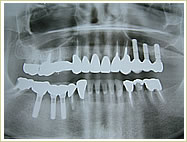

症例 54歳 男性 インプラント埋入数:11本 画像拡大

治療前 治療後